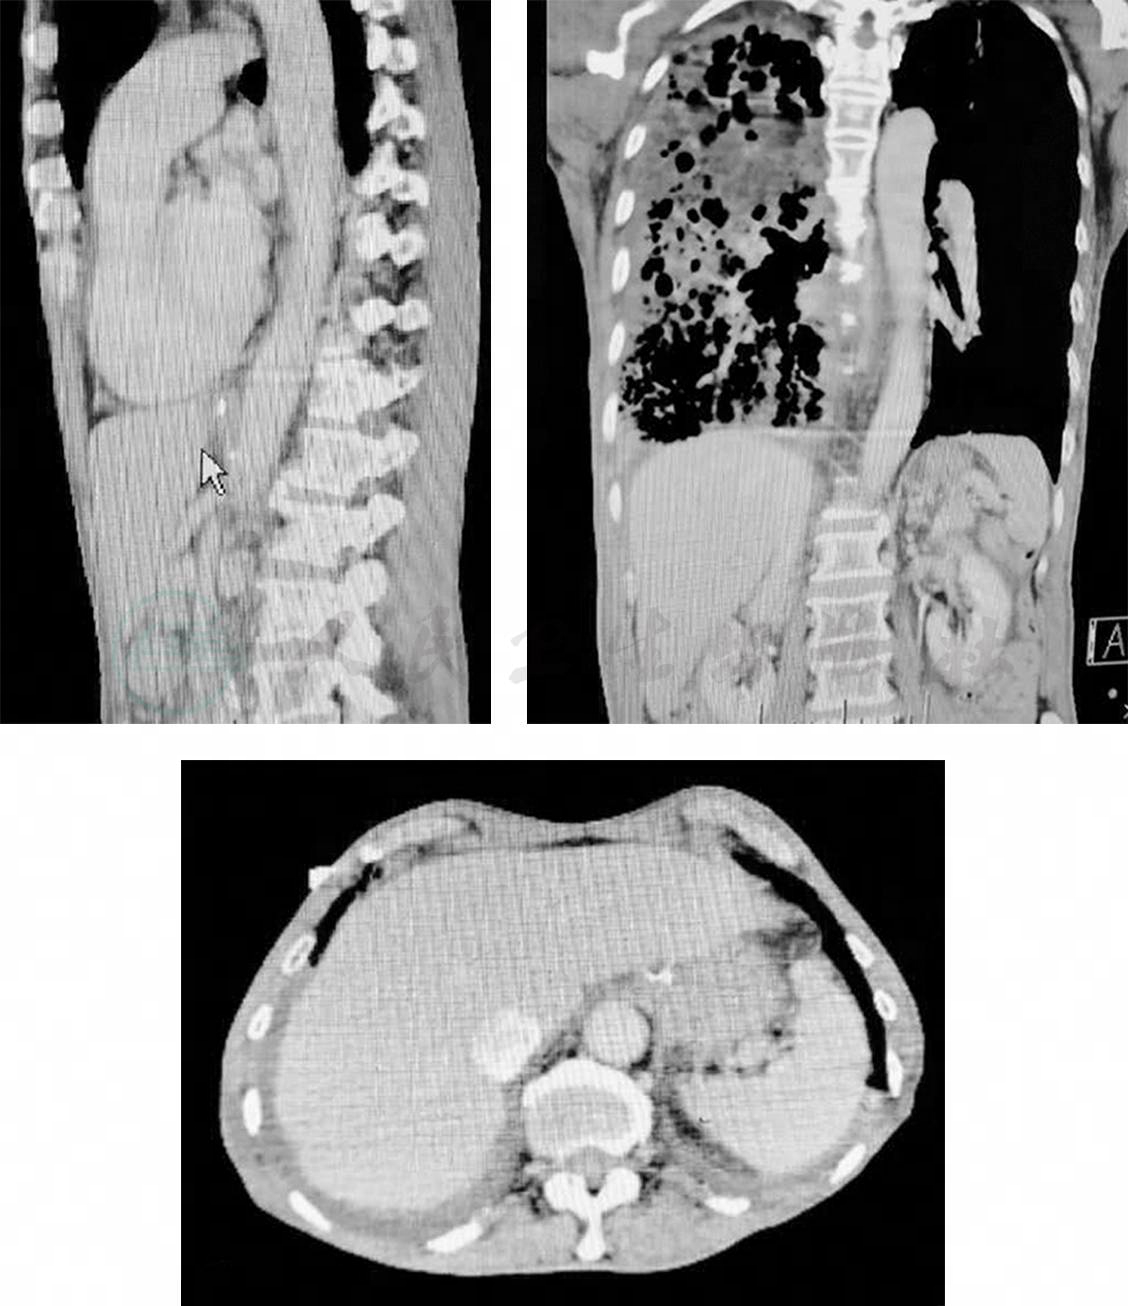

TP 22.3g/L,ALB 14.8g/L,LDH 249IU/L;支气管分泌物pH 8~9;支气管分泌物涂片偶见颗粒状黄色结晶,并将此分泌物做胆红素干化学试验示阳性,考虑此结晶为胆红素颗粒状结晶;支气管分泌物培养(7月24日):洋葱伯克霍尔德菌,鲍曼不动杆菌(药敏:替加环素中介,余耐药);血、胸腔积液、支气管分泌物结果如下(表2);肝胆CT+增强(图5):肝脾胰腺、双肾形态正常,未见明显异常密度及异常强化灶,胆囊未显示,胆囊区见不规则金属密度影,未见腹水征。

图5 肝胆CT+增强(7月20日)